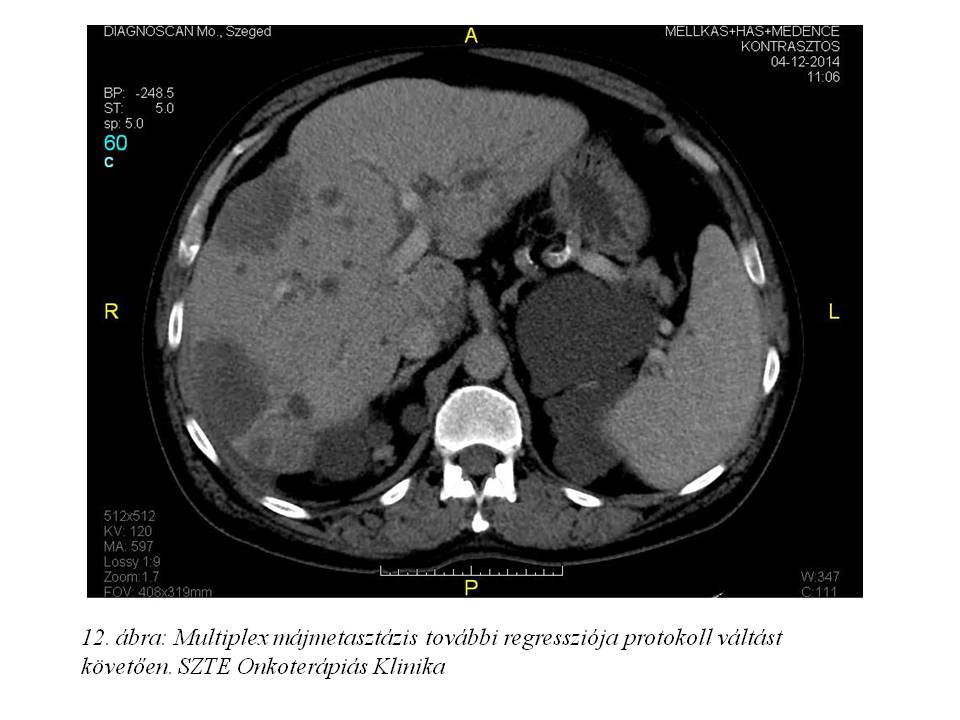

A fentiek értelmében a 16. ciklustól az oxaliplatin adásától eltekintettünk, kezelését DeGramont protokoll (Leucovorin + 5FU bolus + 5FU folyamatos infúzióban) szerint folytattuk. 2014. december 29-ig összesen 11 ciklust kapott. Az ez idő alatt elvégzett re-staging has-kismedence CT további regressziót írt le (2014.08.08. 10. ábra, 2014.10.08. 11. ábra, 2014.12.04. 12. ábra), a mellkas CT-n tüdőmetasztázis továbbra sem detektálható, a tumormarkerek tovább csökkentek (CEA: 0,8 ng/ml, CA 19-9: 7,32 U/ml), májfunkciós enzimek értéke normális.